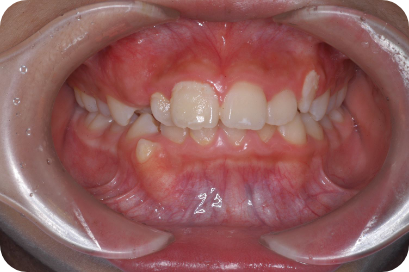

Tさん

Before

After

- 形態:狭いV型の上顎を丸くて広いU型に改善、歯ならび、咬み合わせの改善

- 機能:咀嚼嚥下トレーニング、口腔周囲筋トレーニング、姿勢改善